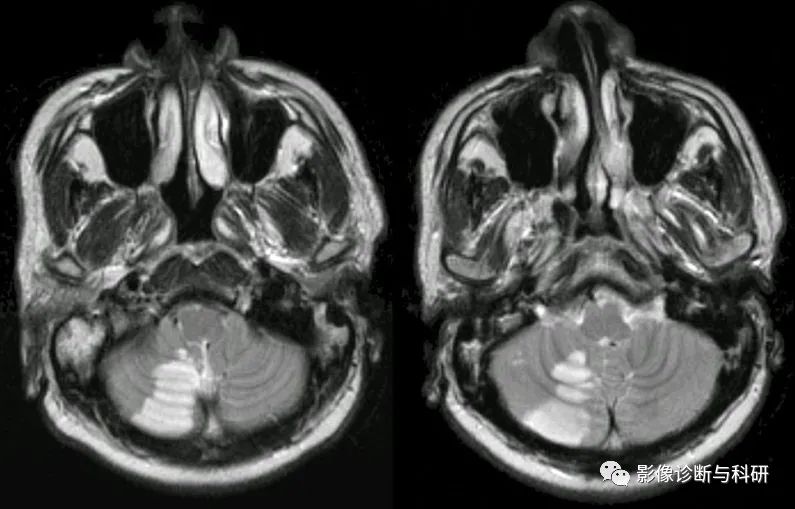

弥散加权图像显示左小脑前下动脉 (AICA) 区域梗死 ( a )。在磁共振血管造影中,左侧 AICA 缺失,而右侧 AICA 清晰可见 ( b )。基础平行解剖扫描磁共振成像(BPAS MRI)显示双侧 AICA 正常(c)